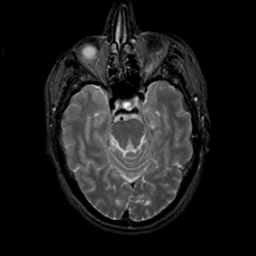

MR Study #19, August 25, 1991 -- Slice #17